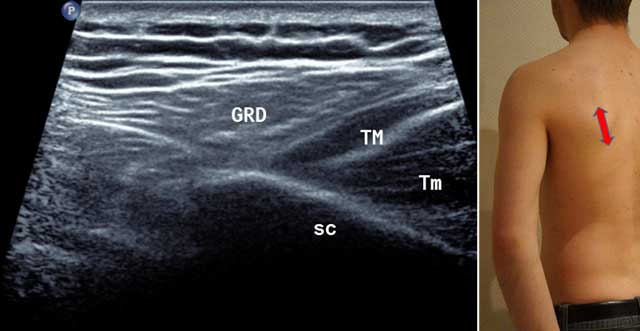

Figure 2

Sagittal oblique view of the scapula (Sc) in external position (red arrow). GRD: Latissimus Dorsi, TM: Teres Major, Tm: Teres minor.